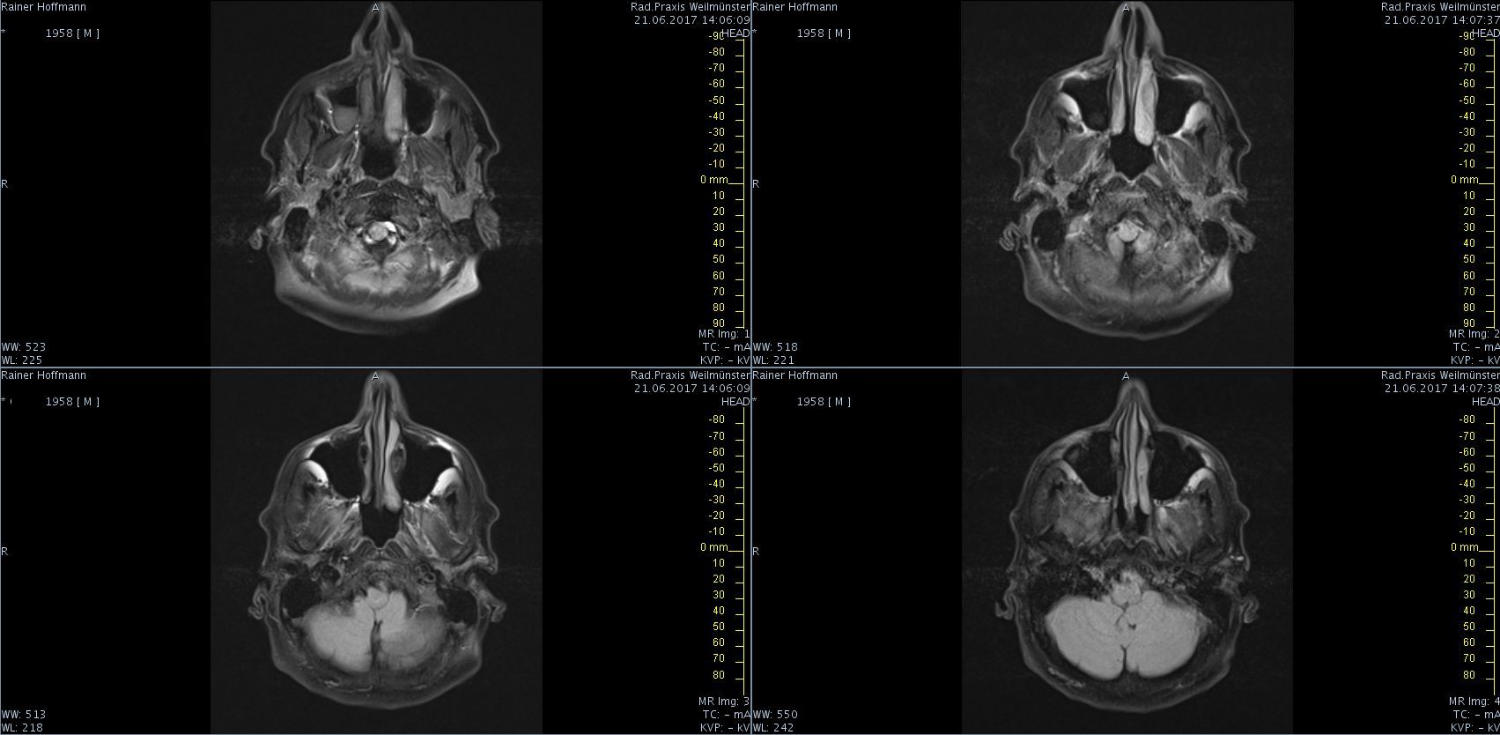

Das ist ja ganz toll, dass Ihr die Seite so schnell gefunden habt. Ich zeige euch jetzt ein ganz, ganz anderes Paßfoto von mir. Es könnte Ähnlichkeiten zu anderen lebenden oder bereits verstorbenen Personen geben. Wenn Ihr das erste Bild oben links anklickt wird es ver- größert dargestellt. Dann kann man mit den Pfeiltasten am unteren Bild- rand durch meinen Kopf blättern. Es gibt nicht viel zu sehen. Vielen Dank an Martina für Ihre Hilfe.

MRT